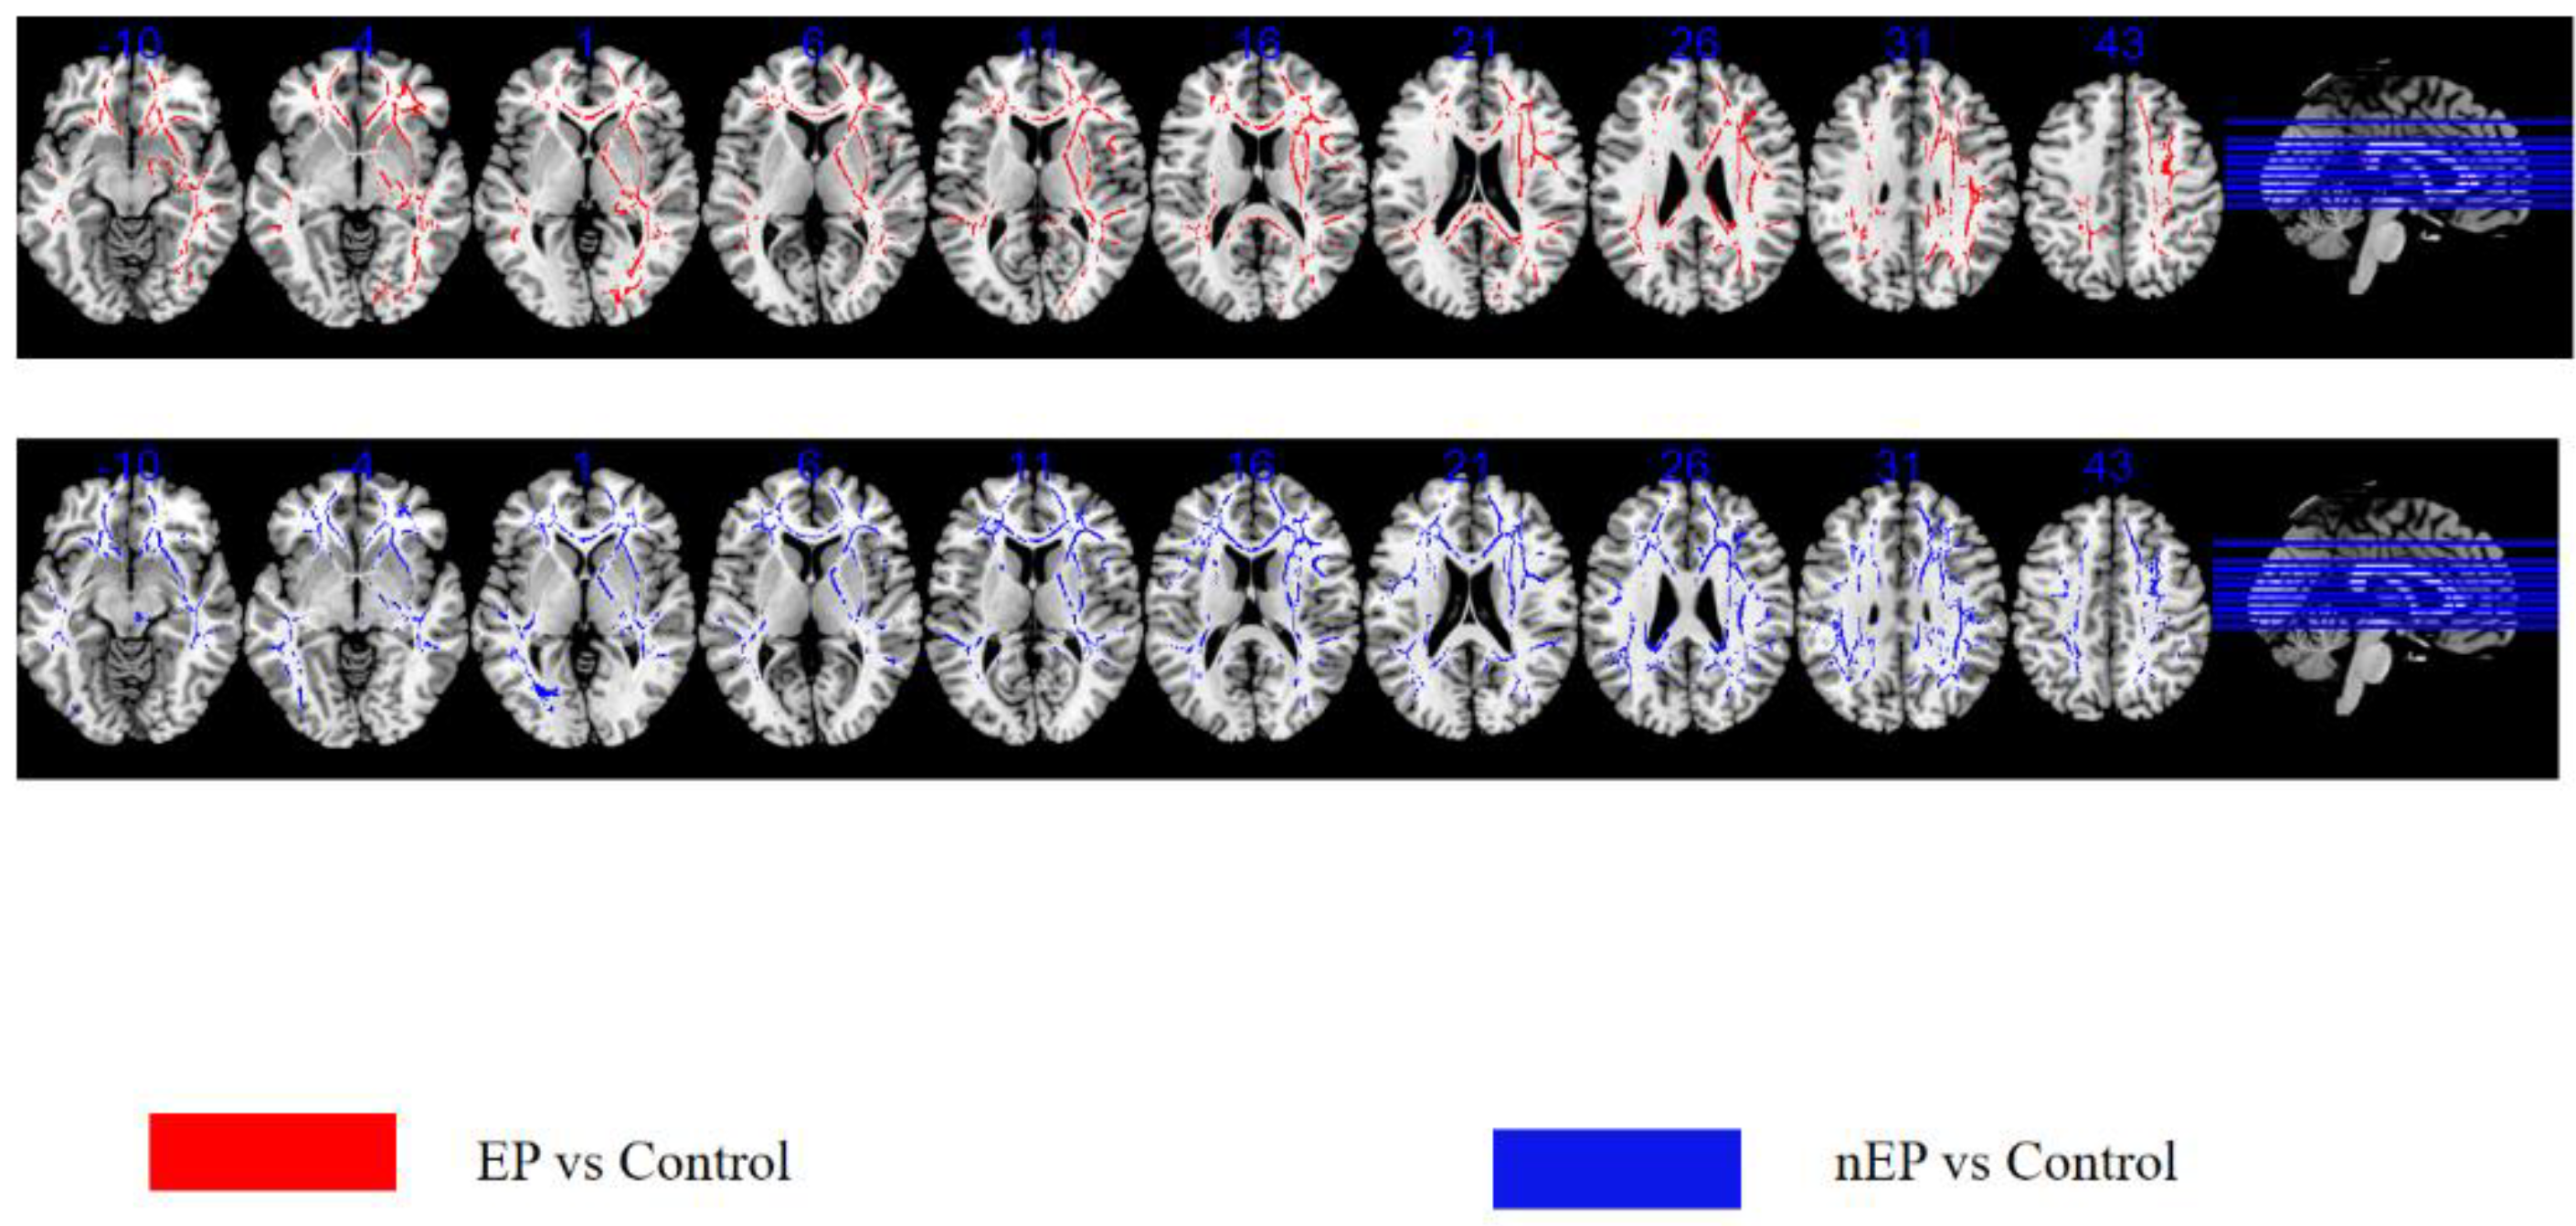

3.3. TBSS-EP Group versus Control

3.4. TBSS-nEP Group versus Control